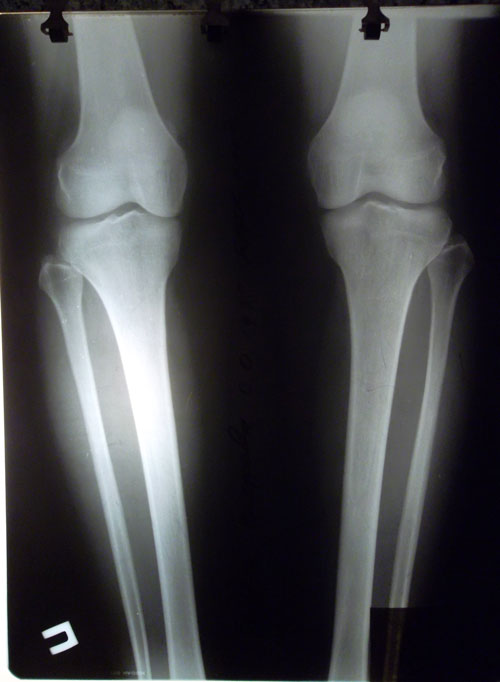

РЕНТГЕН НА 30 - ЫЙ ДЕНЬ С МОМЕНТА ОПЕРАЦИИ.